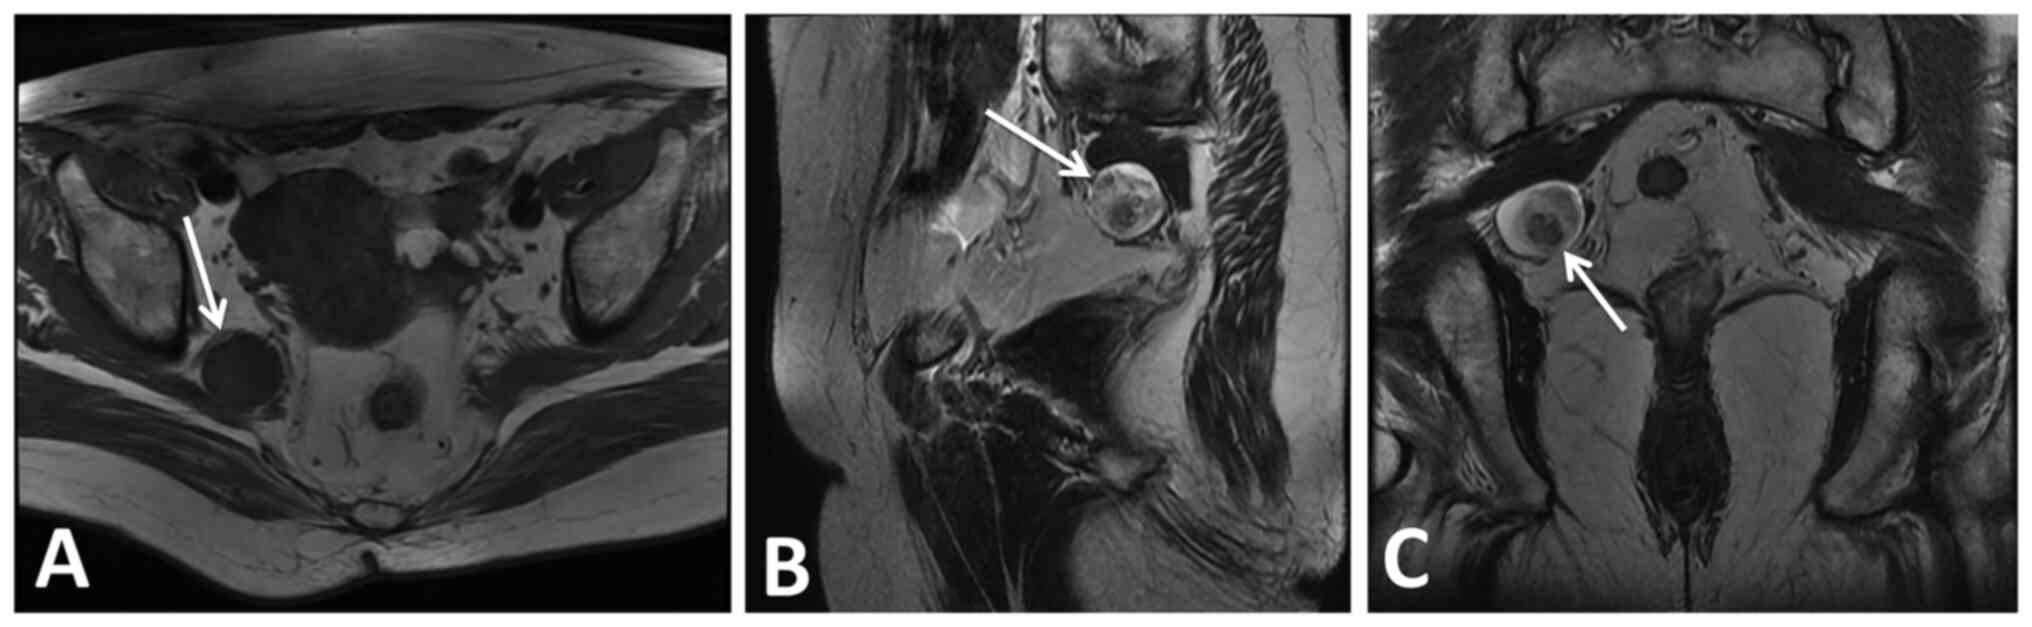

On magnetic resonance imaging (MRI) scans of the abdomen and pelvis, there was a soft-tissue mass (2.6x2.9x2.3 cm) in the right pelvic cavity (Fig. 1A). MRI showed a rounded and nonhomogeneous high signal intensity on T2-weighted images (Fig. 1B and C). On neurological examination, there was no significant motor loss in the affected extremity. Before the operation, the patient was informed of the possibility of conversion to open surgery, as, due to degeneration, bleeding or cystic changes, it may be hard to divide the tumor from the normal nerve. In this case, it may be necessary to convert to open surgery to preserve neurological function. However, if the tumor was considered to be malignant and nerve invasion had occurred, radical surgery would be performed.

Figure 1

Preoperative MRI results. (A) T1-weighted axial MRI of the sciatic nerve schwannoma. (B) T2-weighted sagittal MRI of the sciatic nerve schwannoma. (C) T2-weighted coronal MRI of the sciatic nerve schwannoma. MRI, magnetic resonance imaging.